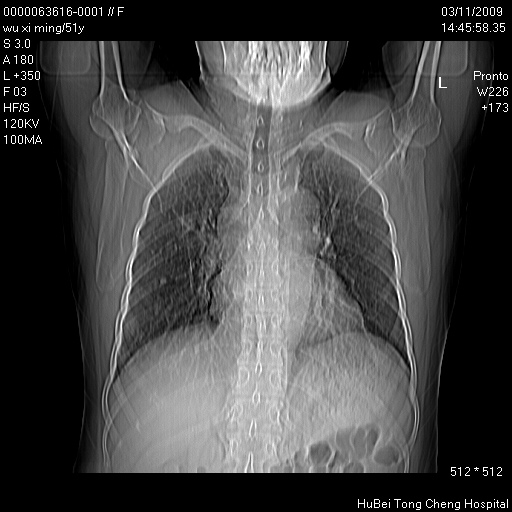

患者 女,51岁。因“胆囊炎,胆囊结石”,行常规术前胸部x线检查发现:右上肺结节病灶,建议行进一步检查。患者无咳嗽、咳痰及咯血等呼吸道症状,近期出现背部疼痛不适。

胸部ct轴位平扫(层厚10mm,螺距1.5,重建间隔10mm;部分层面:层厚3mm,螺距1.0,重建间隔3mm),图像如下: